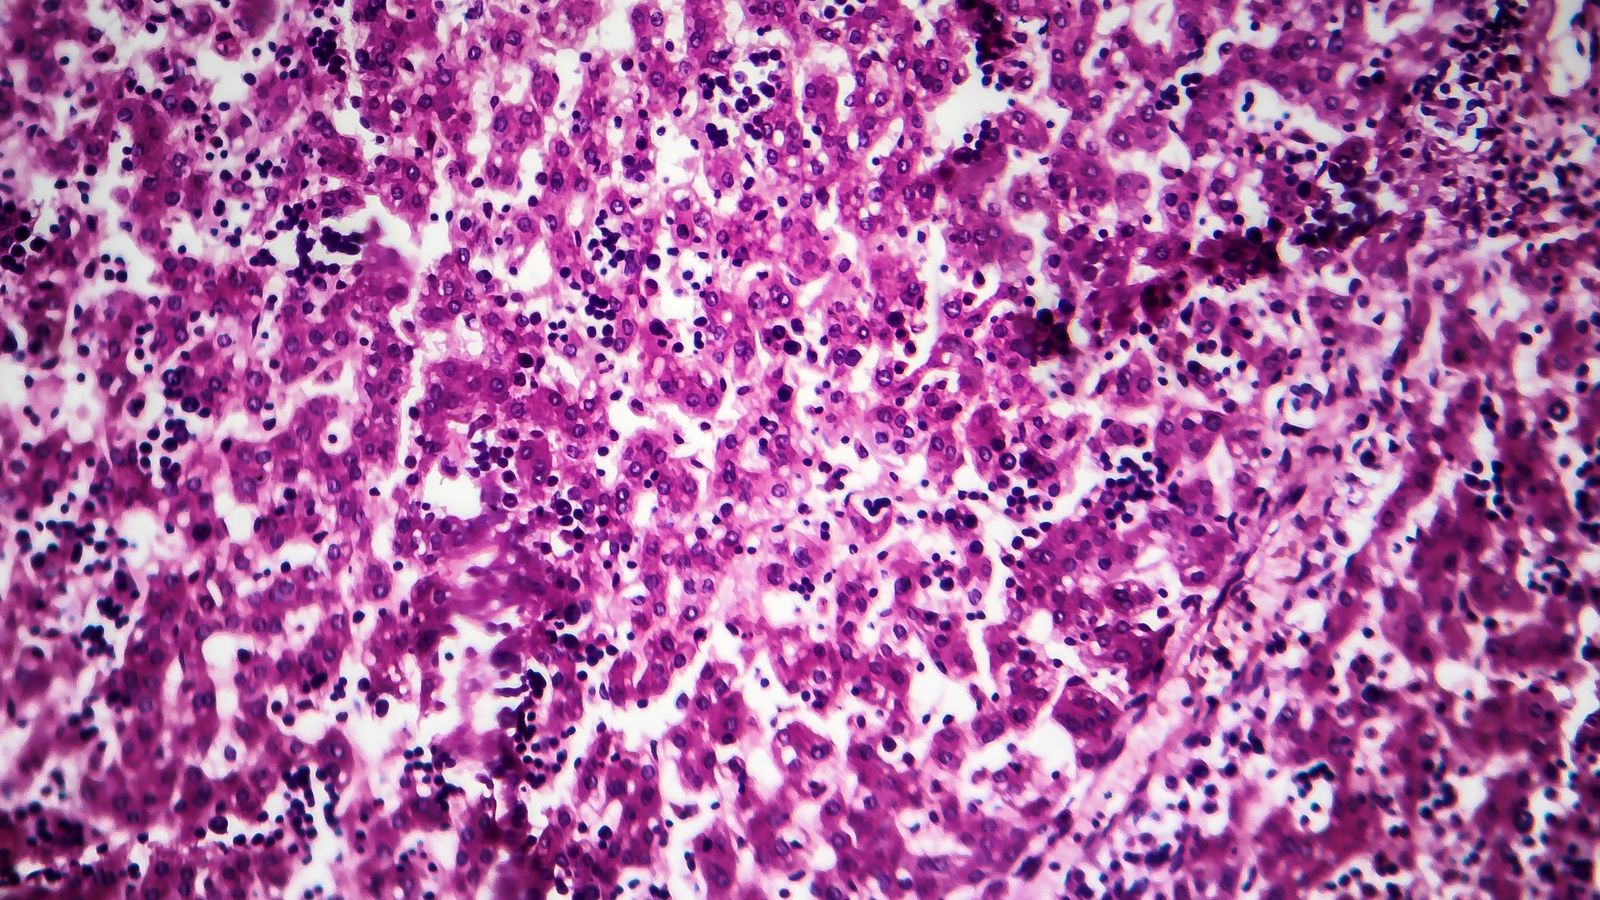

Fins a 37 casos d'hepatitis infantil aguda d'origen desconegut registrats pràcticament la primera meitat de 2022 i repartits en deu autonomies. És l'últim balanç que ha donat a conéixer el Centre de Coordinació d'Alertes i Emergències Sanitàries (CCAES), en què apel·la a la necessitat de "mantindre la intensitat en la vigilància i les actuacions que ja s'estan realitzant" amb l'objectiu de "confirmar o descartar si existeix un increment de casos d'hepatitis no filiada respecte del que es pot esperar". La immensa majoria dels quasi quaranta casos detectats es donen en xiquets sans menors de sis anys, sobretot xiquetes, sense relació entre si. Un ha requerit un trasplantament de fetge.

Des que a principis d'abril s'activara l'alerta per l'aparició de deu casos d'hepatitis aguda greu d'etiologia desconeguda en xiquets menors de deu anys (entre onze mesos i cinc anys) prèviament sans a Escòcia, vint països europeus n'han notificat un total de 449. D'aquesta quantitat, 37 s'han confirmat a Espanya, xifra que eleva en set l'última actualització del 27 de maig.